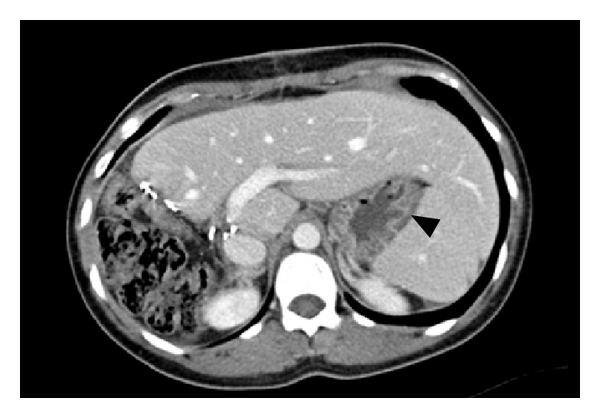

KS, a 31-year-old woman with mild gastroesophageal reflux disease requiring no home medications, presented for planned open left hepatectomy (our preferred technique at the time) for liver donation. During the procedure, a replaced left hepatic artery was visualized and dissected to the level of its origin from the left gastric artery. To completely mobilize the replaced artery, neurovascular branches supplying the lesser curvature of the stomach were divided. Upon examination of the hepatic hilum, a standard left hepatic artery was found, as well as a small segment-4 artery from the proximal right hepatic artery. These additional arteries were not seen on preoperative imaging. Due to concern for increased risk of graft failure, the decision was made to convert to a right hepatectomy. The operation proceeded without complications. After removal of the right lobe graft, omentum and colon were placed in the resection bed, and Seprafilm adhesion barrier was applied to the cut liver surface. During the first postoperative week, the patient complained of nausea, heartburn, reflux, and nonbilious vomiting. The patient gradually improved with medical management including a proton pump inhibitor, sucralfate, and metoclopramide, and she was discharged home on postoperative day (POD) 9. On POD 31, the patient was readmitted for severe nausea, bilious vomiting, and burning epigastric pain. A computed tomography (CT) scan of the abdomen did not suggest bowel obstruction or adhesion formation between the stomach and cut liver surface (Figure 1). Endoscopy revealed retained food products in the stomach, and a gastric emptying study demonstrated absent emptying over one hour (Figure 2). Following initial improvement with medical management as described above, the patient experienced worsening emesis on POD 43 with solid food trial. During repeat endoscopy, 200 units of botulinum toxin were injected at the pylorus. Afterward, the patient experienced no further emesis and tolerated oral medications. An upper gastrointestinal series with small bowel follow-through showed no abnormalities. The patient was discharged home on POD 49. She underwent a repeat gastric emptying study one week after discharge, which showed marked improvement and normal gastric emptying (Figure 3). In subsequent follow-up, she reports feeling well and eating normally. She is currently over four years postdonation.

The case of KS is particularly noteworthy in the fact that we initially performed the dissection for a left hepatectomy but ultimately used a right lobe graft. As a result, the resection bed was far removed from the stomach, and the cut liver surface was faced away from the stomach. The absence of apposition significantly decreases the probability of adhesion formation between the stomach and the cut surface of the liver. Indeed, we did not find evidence of postoperative gastrohepatic adhesions on CT scan for KS.